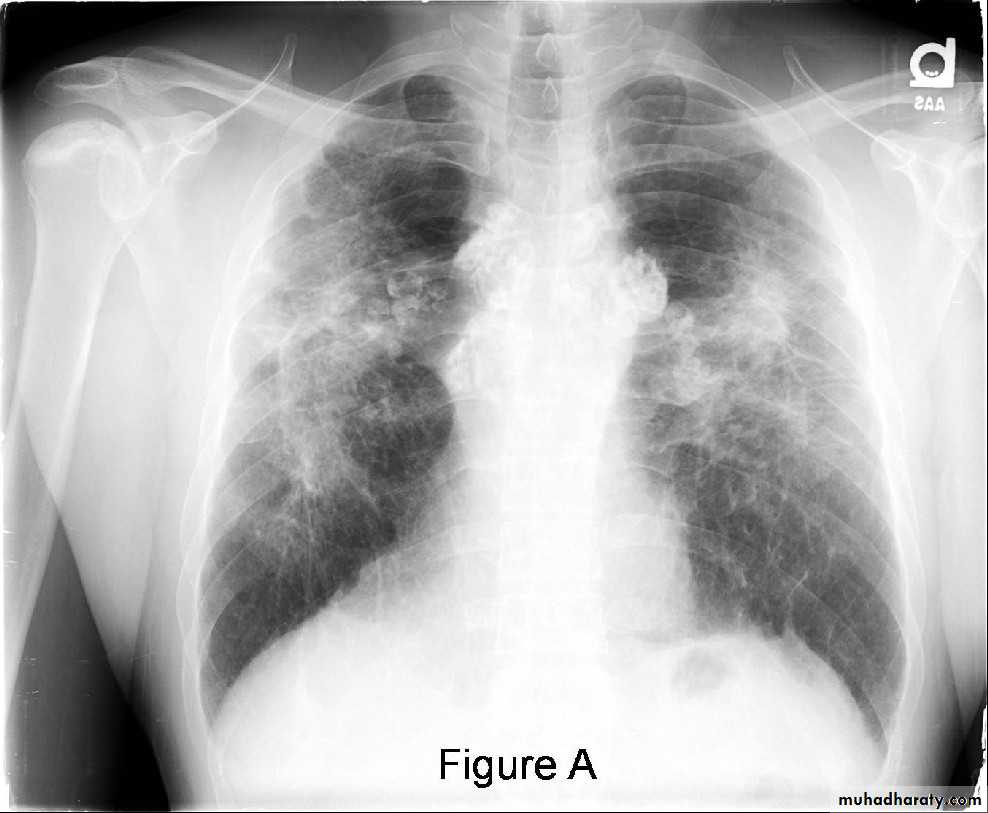

Abnormal chest X-ray at presentation with lower zone bi-basal reticular and reticulonodular opacities. 'honeycomb' appearance in advanced disease.

HRCT may be diagnostic, demonstrating a patchy, predominantly peripheral, subpleural and basal reticular pattern with subpleural cysts (honeycombing).

Coal dustSimple coal worker's pneumoconiosis

Complicated pneumoconiosisCaplan's syndrome